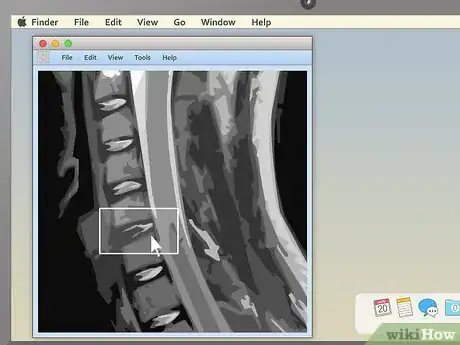

3Pick an appealing series layout. MRI programs almost always have the ability to display more than one image at once. This makes it convenient for doctors to compare different views of the same area or even MRIs taken at different times. For most non-doctors, it's easiest to simply choose a one-image-at-a-time layout and cycle through the images individually. However, there should be onscreen instructions to show two, four, or many more images at once, so feel free to play around with this feature.

-

4Use the section-cut line to see where cross-sections are located. If you display a cross-sectional image along with a sagittal or coronal image, you may see a section-cut line on the second image. This will be a straight line running through the image, but it may not be present on all MRIs. If your image does have one, this shows where on the second image the cross section is located. You should be able to move the section cut line toward the center, right or left of the image. This will change the larger layout image to show the body from the new direction of the scan.

- The section-cut line on the layout picture also shows the direction that the image was taken from. For example, if your MRI were a picture of an everyday object, like a tree, the section cut line might show you if the picture was taken from above in a plane, from a second-story window, or from the ground.

5Drag the section-cut line to view new parts of the study. Dragging the section-cut line to a different part of the image allows you to "move around" your MRI images. The image should change your view to the new area automatically.

- For example, if you're viewing a sagittal image of your spine along with a cross section of one of your vertebrae, moving the section-cut line may allow you to cycle up and down through the various vertebrae above and below it. This can be useful for locating problems like herniated discs.